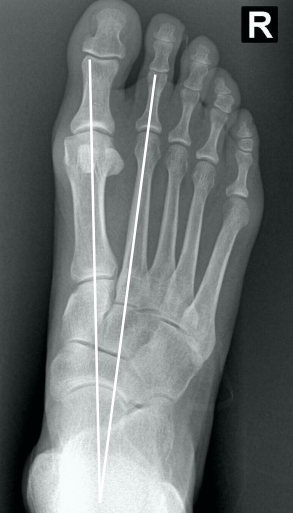

16

• Na radiografia em AP com carga, como é traçado o ângulo intermetatarsal?

A

• Ângulo entre o eixo longo do 1° e do 2° raio

• Normal → até 9°

• Leve → 9° a 12°

• Moderado → 13° a 15°

• Grave → > 16°

17

• Na radiografia em AP com carga, como é traçado o ângulo de valgismo do hálux (metatarsofalângico)?

• Ângulo entre o eixo longo do 1° mtt e o eixo longo da falange proximal

• Normal → até 15°

• Leve → < 25°

• Moderado → 25° a 40°

• Grave → > 40°

20

• Classificação de Mann e Coughlin:

Se baseia nos ângulos radiográficos

• Legenda:

• AVH = ângulo de valgismo do hálux (metatarsofalângico)

• AIM = ângulo intermetatarsico

• Bizu → Memorize o moderado → pra cima é leve e pra baixo é grave